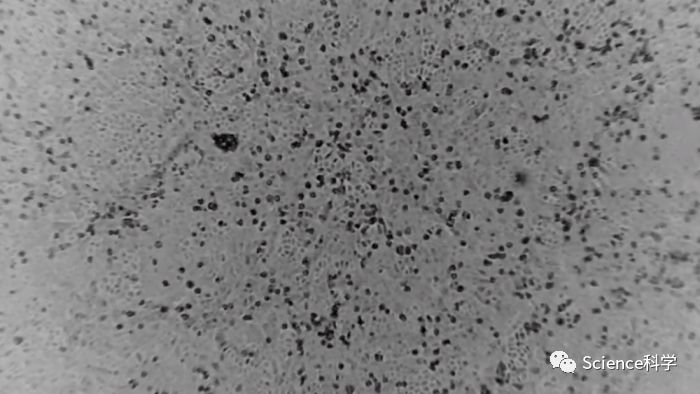

据了解,科学家们利用同步辐射--一种特别明亮的X射线辐射--对组织结构进行了高分辨率的成像,然后以三维方式显示。为了做到这一点,他们使用了哥廷根大学在汉堡的德国电子同步加速器DESY建立和运行的特殊X射线显微镜。当他们检查严重形式的COVID-19疾病的影响时,他们在心肌组织中的毛细血管(微小血管)层面观察到了明显的变化。

跟健康的心脏相比,受严重疾病影响的组织的X射线成像显示了一个充满分裂、分支和环形的网络,这些网络由于新血管的形成和分裂而被混乱地重塑了。这些变化是COVID-19中肺部损伤的主要驱动因素之一的第一个直接视觉证据:组织中一种特殊的“Intussusceptive angiogenes(意为新血管的形成)”。